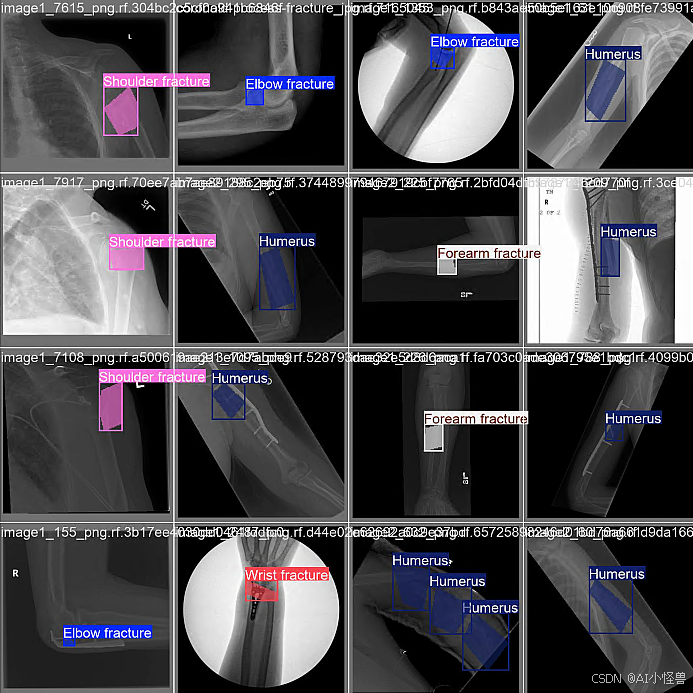

nc: 7 names: ['肘部阳性', '手指阳性', '前臂骨折', '肱骨骨折', '肱骨', '肩部骨折', '手腕阳性']细节图:

names: ['Elbow fracture', 'Finger fracture', 'Forearm fracture', 'Humerus fracture', 'Humerus', 'Shoulder fracture', 'Wrist fracture']

预测结果: